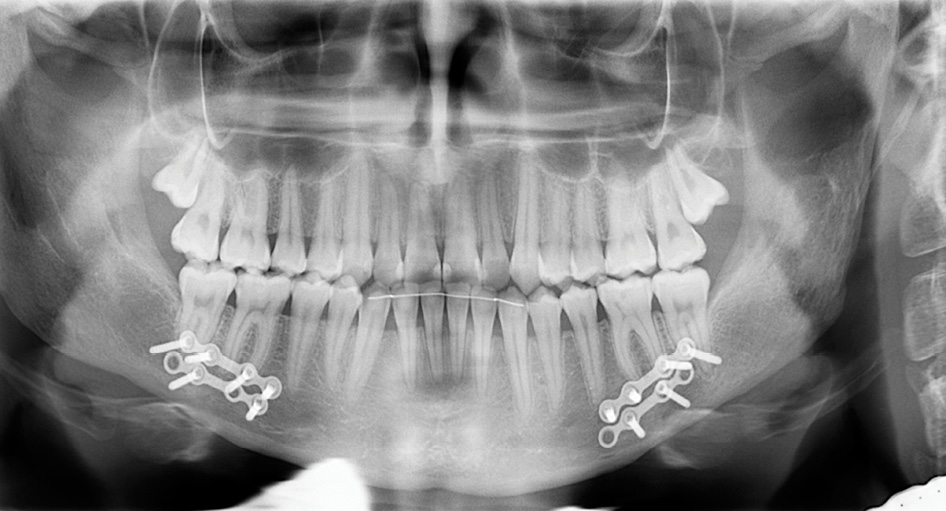

На ОПТГ наблюдается 30 постоянных зубов, отсутствуют зубы 3.8, 4.8. (рисунок 3). Анализ телерентгенограммы головы в боковой проекции (ТРГ) в программе Dolphin Imaging (США) (рисунок 4) показал: нормальные значения угла SNА = 81,2° (норма = 82°±2) и длины основания верхней челюсти (ANS-PNS) = 49,7 мм (норма = 51,6 мм); увеличение угла SNB = 87,1° (норма = 80°±2) и длины основания нижней челюсти (Pg-Go) = 85,7 мм (норма = 74,3 мм); отклонение и отрицательное значение угла ANB = -6 ° (норма = 1±1°); Wits-число равное -8.7 (в норме 1±1), что подтверждает наличие скелетной формы мезиальной окклюзии, обусловленной передним положением и макрогнатией нижней челюсти при нормогнатии и правильном положении верхней челюсти относительно переднего отрезка черепа. Это позволяет предположить наличие изменений в сосудах головы и шеи и гемодинамики в них. Для подтверждения диагноза была проведена ультразвуковая допплерография (триплексное сканирование) сосудов головы и шеи справа и слева (рисунок 5).

Рисунок 3. Ортопантомограмма пациентки Т., 18 лет, с мезиальной окклюзией гнатической формы до операции на нижней челюсти.